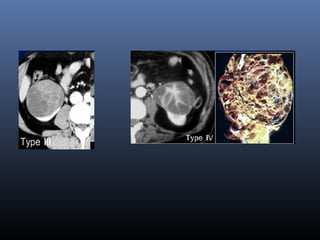

 Phân lo i c a BOSNIAK :ạ ủ

Type III, IV (+) t n th ng th phát t i gan,ổ ươ ứ ạ

ph i => nang chuy n sang ác tínhổ ể

Type III Nang nghi ng :ờ

Nhi u vách d y+/hay thành nang d y, gi i h n không đ uề ầ ầ ớ ạ ề

Các vôi d y +/hay không đ u, đ m đ d ch cao (>20UH)ầ ề ậ ộ ị

Thành và vách b t thu c c n quangắ ố ả

+> ph u thu t sinh thi tẫ ậ ế

Type IV Ung th u th n (d ng nang)ư ậ ạ

Thành nang d y, không đ u -Có ch i, sùi , các n tầ ề ồ ố

Vách nang và các ch i, n t b t thu c c n quang (>50UH)ồ ố ắ ố ả

=> Ph u thu t c t th nẫ ậ ắ ậ

Type III

Type IV